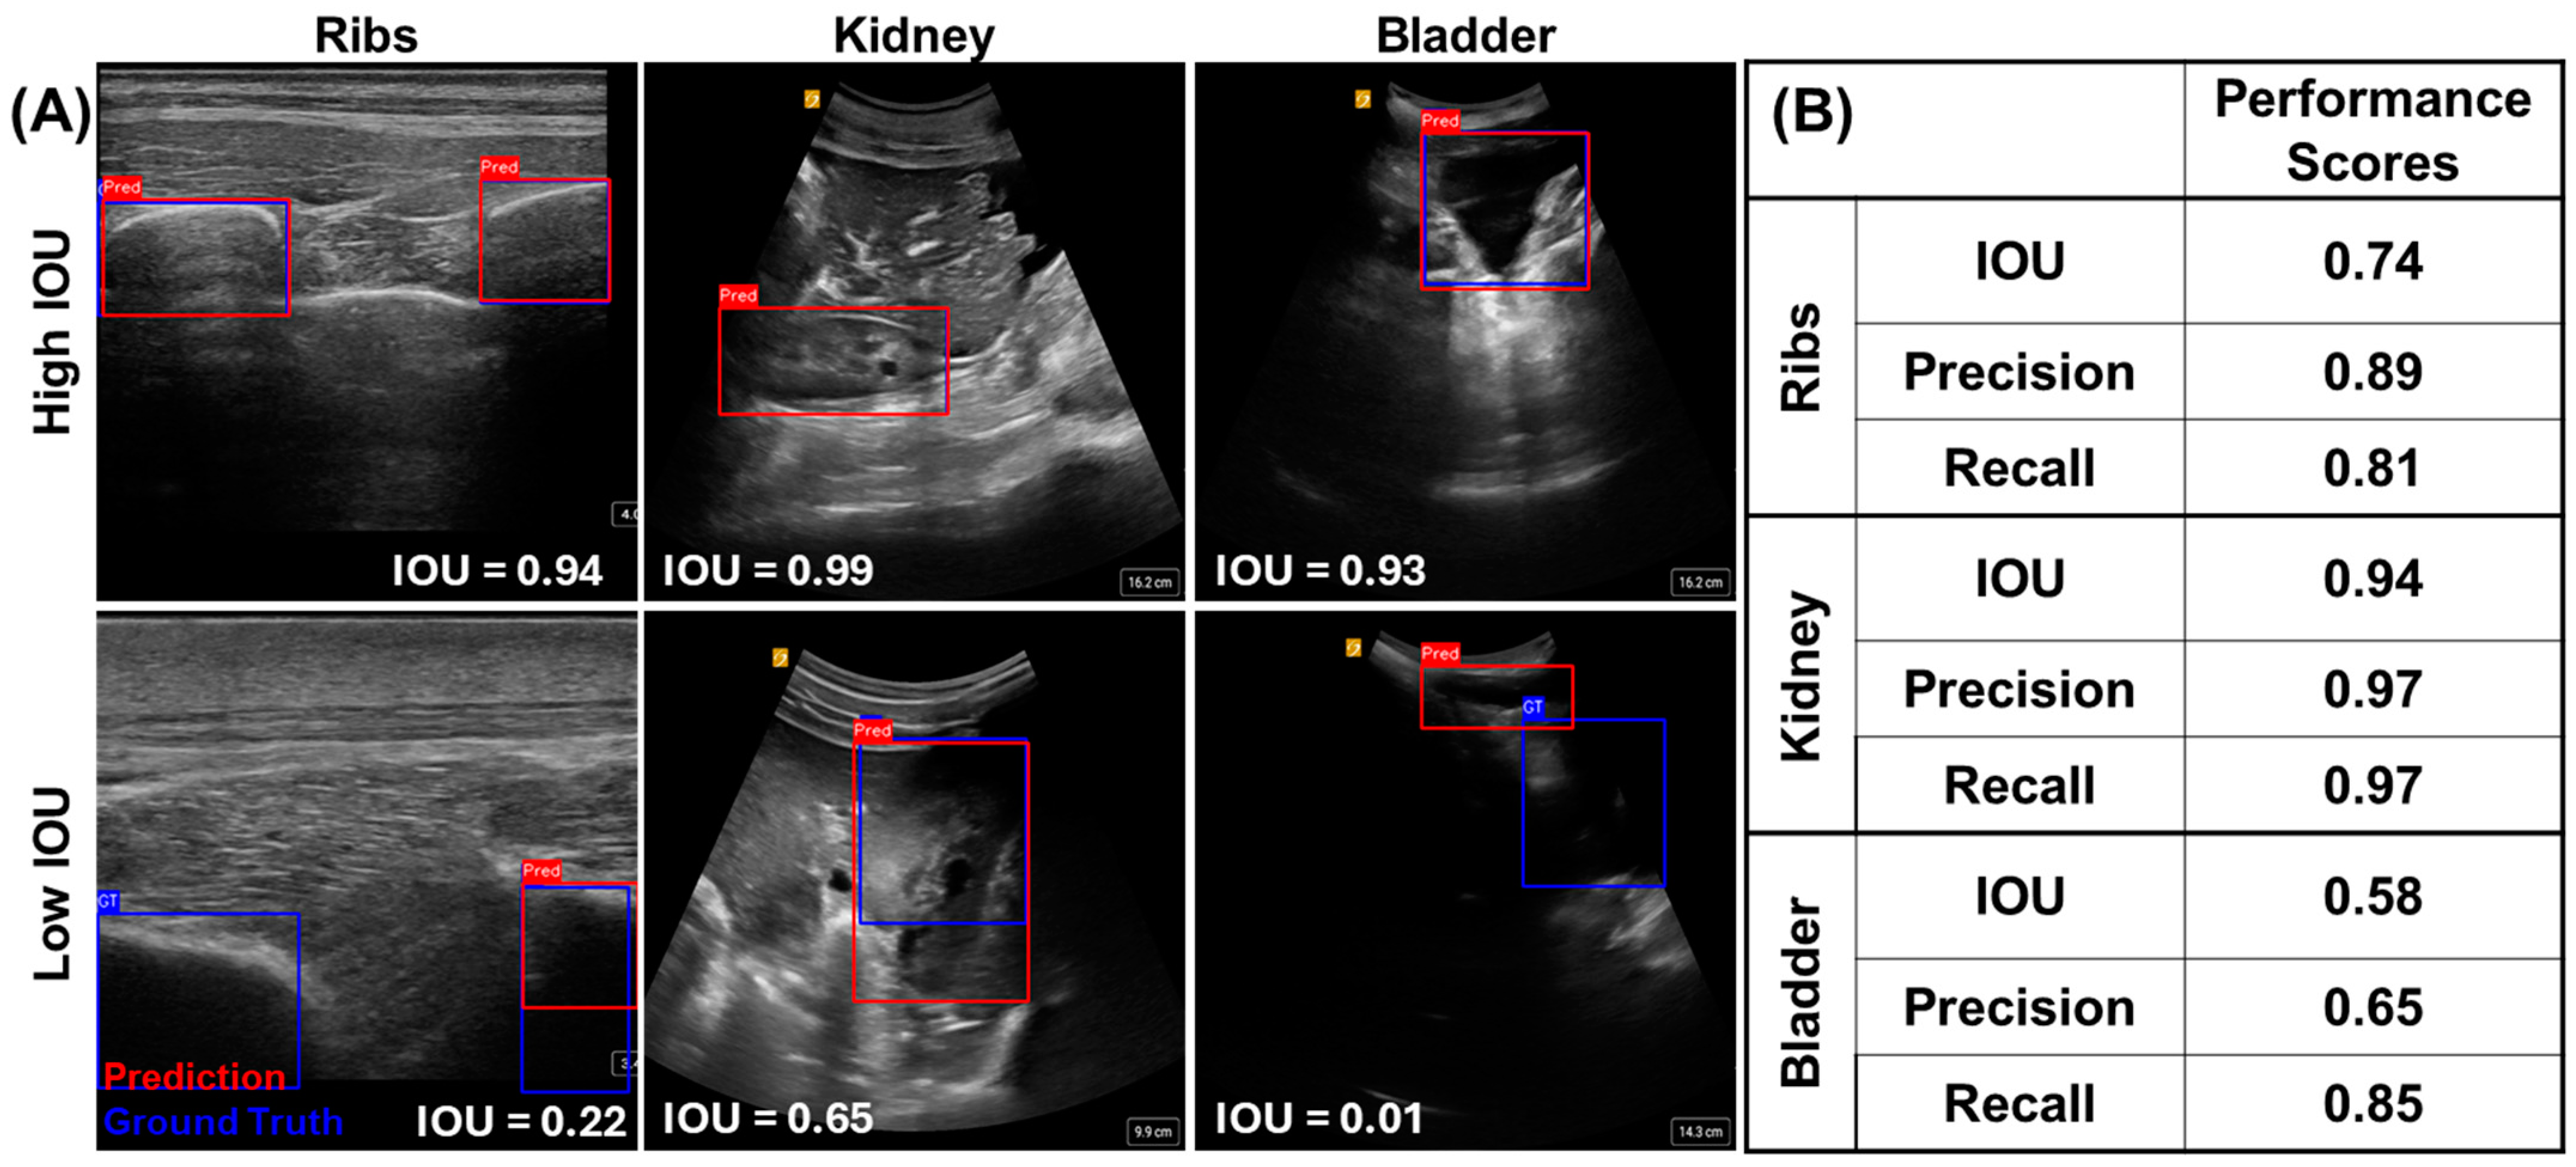

For each guidance model trained, model performance was evaluated against a test dataset comprising images from subjects not included in the training data. Examples of high and low IOU scores are shown for each guidance model in Figure 7A. The resulting average IOU scores varied across each model, with kidneys having the highest score at 0.94, followed by the ribs and bladder at 0.74 and 0.58, respectively (Figure 7B). The precision and recall metrics were also strong for each guidance model, apart from precision for the bladder model, which was only 0.65 (Figure 7B). A higher false-positive rate due to the pixels being identified as bladder in the model’s prediction but not in the ground truth image resulted in this lower score for the bladder model. Overall, each model was trained at variable performance levels and was able to correctly identify anatomical features to aid with proper eFAST US image acquisition.

Figure 7.

Guidance AI performance for each anatomical location. (A) Representative images are shown for high and low IOU scores for rib, kidney, and bladder predictions. (B) Testing performance scores for each anatomical guidance model for IOU, precision, and recall metrics.